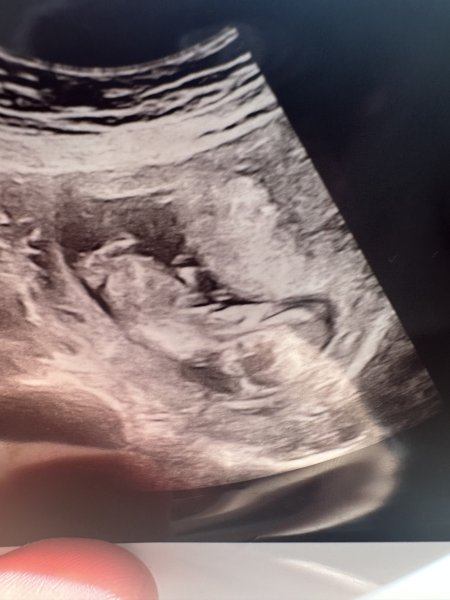

Şu isaretledigim yere dikkatli bakabilir misiniz orası cinsiyet ama biseye benzetemedim

Selamlar bi tanem vallahi tam olarak hatta hiç bişi göremiyorum daha daha doğrusu, ilgili resimdeki veri, cinsiyet tahmini için yeterli değil. Bak hemen aşağıdaki nub teorisine göre bebek cinsiyet tahmini yapmak istiyorum ama o alan yok aşağıdaki konuyu incele bitanem.